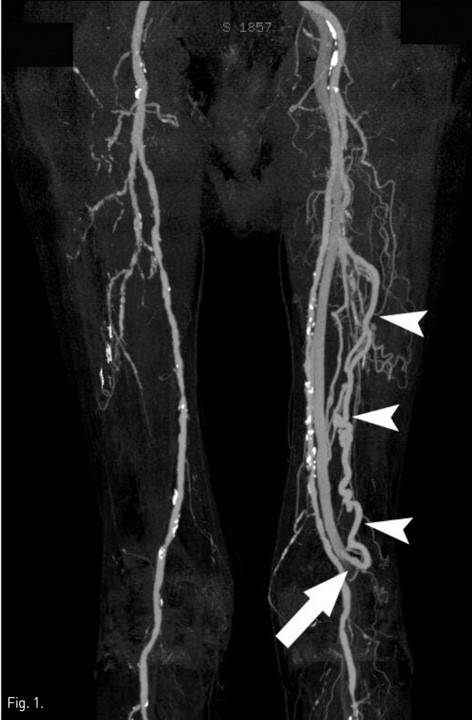

당뇨병으로 30년 동안 인슐린으로 혈당조절중인 환자로 좌측 무지의 허혈성 변화 등으로 당뇨 합병증에 의한 말초혈관의 동맥경화성 변화가 의심되어 양측 하지의 CT angiography(CTA)를 시행하였다. 양측 하지의 CTA에서 양측 슬하동맥의 석회화를 동반한 다발성 협착병변들이 있었다. 또한 대퇴골의 원위부 부근에 깊은 넙다리동맥(deep femoral artery)에서 기시하는 비정상적으로 커진 분지동맥과 대퇴정맥(femoral vein) 사이에 비정상적인 동정맥루가 확인되었다(Fig. 1). 이 환자는 좌측 슬하동맥의 다발성 동맥경화성 협착병변에 대해 풍선카테터와 스텐트를 이용한 혈관내 치료를 우선 시행하였다. 이 후 좌측 deep femoral artery과 femoral vein 사이의 동정맥루 치료를 위해 의뢰되었다.

Fig. 1.

CT angiogram shows an enlarged peripheral branch of the deep femoral artery (arrowheads), which communicates with the femoral vein via the large arteriovenous fistula (arrow).